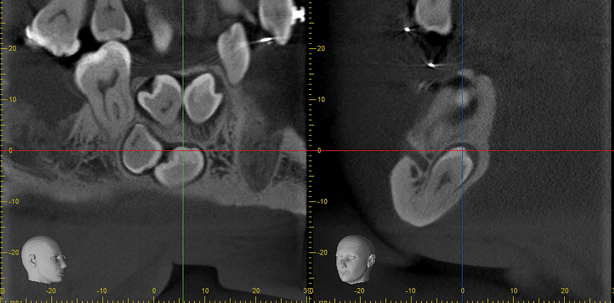

DVT-Aufnahmen: Mesiodens OP-Zugang von nasal (links)/Präoperative Darstellung des N. alveolaris inferior (rechts).